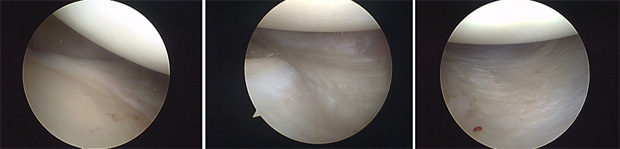

As microperfurações ou microfraturas buscam criar um revestimento fibrocartilaginoso em uma área restrita com ausência de cartilagem e exposição do osso subcondral. Sendo assim, a mosaicoplastia tem o objetivo de criar um revestimento com cartilagem hialina de área doadora do joelho para a cobertura do defeito condral.

Mostramos ao lado um caso de um paciente masculino de 33 anos com uma lesão osteocondral cística do côndilo femoral medial do joelho. O paciente apresentava dores de forte intensidade e derrames articulares de repetição.